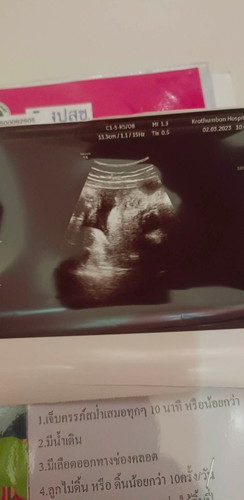

แม่ๆคนไหนดูเป็นบ้างคะว่าคือส่วนไหนของลูก

พอดีเราท้องแรกดูไม่เป็นเลยค่ะ

ดูไม่ออกเลยค่ะไม่ค่อยชัด มีรูปอื่นไหมคะ